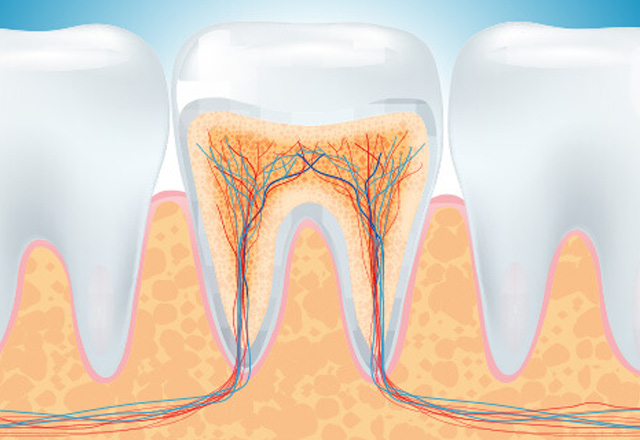

Our dental clinic offers a full range of endodontic treatments (Root canal therapy) for children and adults Our clinic offers the highest